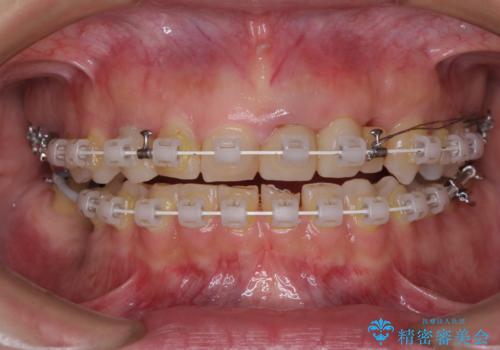

- 右下の奥歯が痛く、全体的に咬み合わせがおかしい気がするとのことで来院された患者様です。

診察したところ、上顎前歯に過剰歯があることで上顎歯列が大きくなり、上下の歯が奥歯の一部でしか咬み合っていない状態でした。

咬み合わせ改善のため、前歯の過剰歯を抜去し、ワイヤー矯正にて歯列と咬み合わせることとしました。

左上の奥歯のブリッジや前歯のセラミッククラウンはいったん除去し、矯正治療後に補綴治療を行うこととしました。